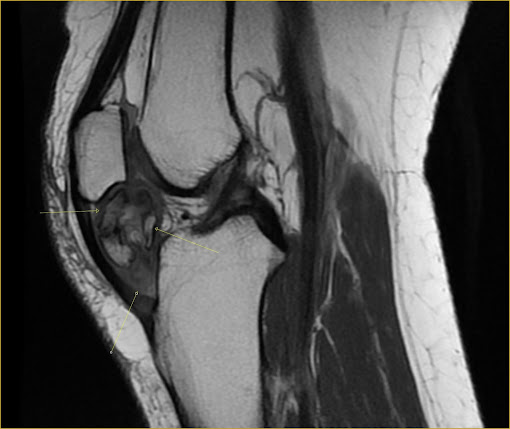

Soft tissue CHONDROMA of the Hoffa fat pad.

MRI. AX and SAG PD and T1. Heterogeneous expansive lobulated lesion with areas of ossification in Hoffa's fat pad.